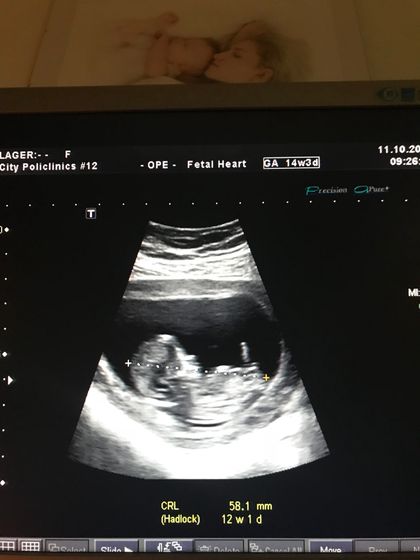

Наконец я сходила на первый скрининг 11 октября. Очень волнительно увидеть своего ребёнка первый раз так чётко, как будто он уже большой, пол даже не предположили конечно))) Проходила скрининг от центра планирования в поликлинике 12 на Академика Комарова, врач мне совсем не понравилась, молчала все время, ни разу не улыбнулась, но главное сказала что все у меня нормально, и это главное. Жаль только мужа отказалась пускать.